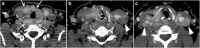

Focal and diffuse thyroid abnormalities are commonly encountered during the interpretation of computed tomography (CT) exams performed for various clinical purposes. These findings can often lead to a diagnostic dilemma, as the CT reflects the nonspecific appearances. Ultrasound (US) examination has a superior spatial resolution and is considered the modality of choice for thyroid evaluation. Nevertheless, CT detects incidental thyroid nodules (ITNs) and plays an important role in the evaluation of thyroid cancer. In this pictorial review, we cover a wide spectrum of common and uncommon, incidental and non-incidental thyroid findings from CT scans. We also discuss the most common incidental thyroid findings, best practices for their evaluation, and recommendations for their management. In addition, we explore the role of imaging in the assessment of thyroid carcinoma (before and after treatment) and preoperative thyroid goiter, as well as localization of ectopic and congenital thyroid tissue.

Teaching points: • Thyroid disorders tend to have non-specific CT appearances. • ITNs are common on neck CT. • ITN management depends on nodule size, age, health status, lymphadenopathy, and invasion. • CT is used in assessment of cancer extension, mass effect, invasion, and recurrence. • CT plays a role in preoperative planning in patients with symptomatic goiter.